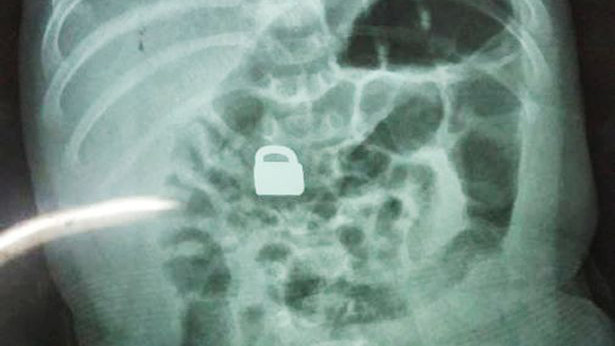

Hình chụp X-quang cho thấy chiếc ổ khóa nằm gọn trong bụng của bé 2 tháng tuổi

Ngay lập tức, họ đưa con tới bệnh viện kiểm tra. Các bác sỹ ngạc nhiên khi thấy chiếc ổ khóa nằm gọn trong ruột của em bé. Do chiếc ổ khóa có kích thước khá nhỏ, chỉ 1,5 x 0,9 cm, to hơn móng tay người lớn một chút, nên các bác sỹ quyết định không mổ lấy dị vật mà để bé tự đào thải.

Theo truyền thông địa phương, 5 ngày sau đó, chiếc khóa đã được bài tiết ra ngoài. Kiểm tra y tế cũng xác nhận em bé sơ sinh không gặp vấn đề gì về sức khỏe.